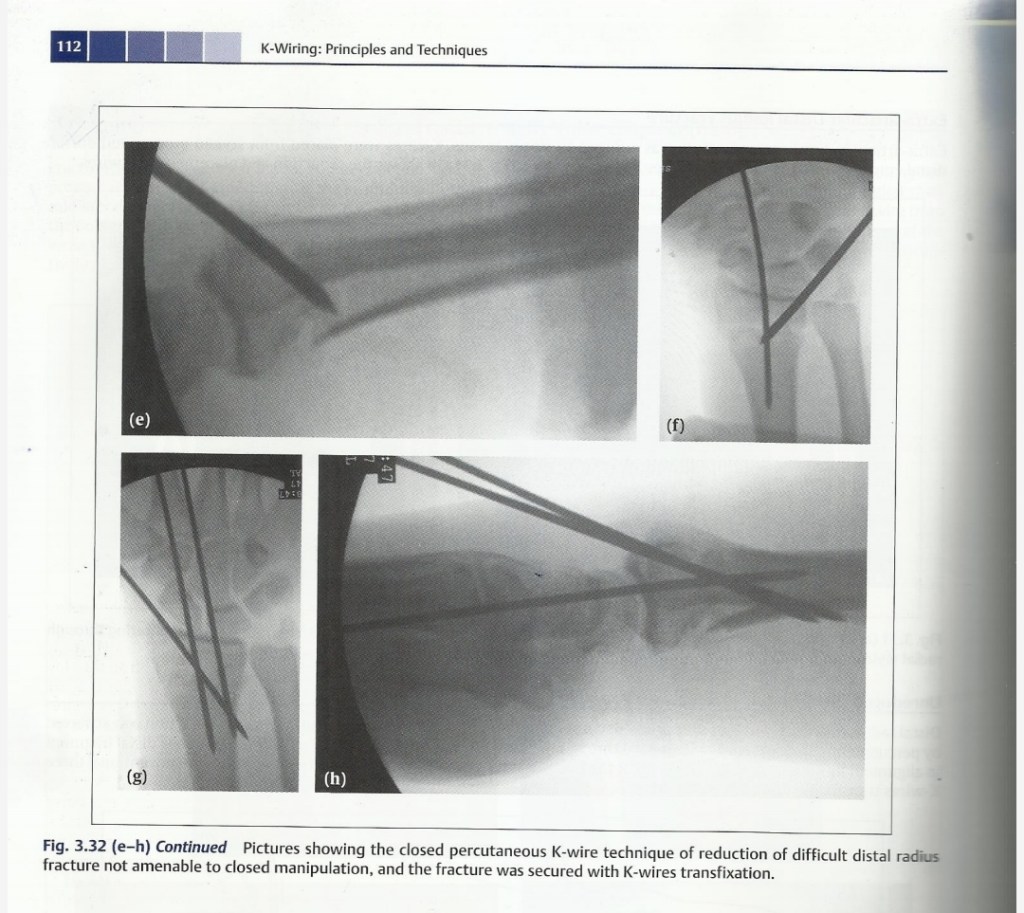

Lecture Pediatric Orthopedic injuries